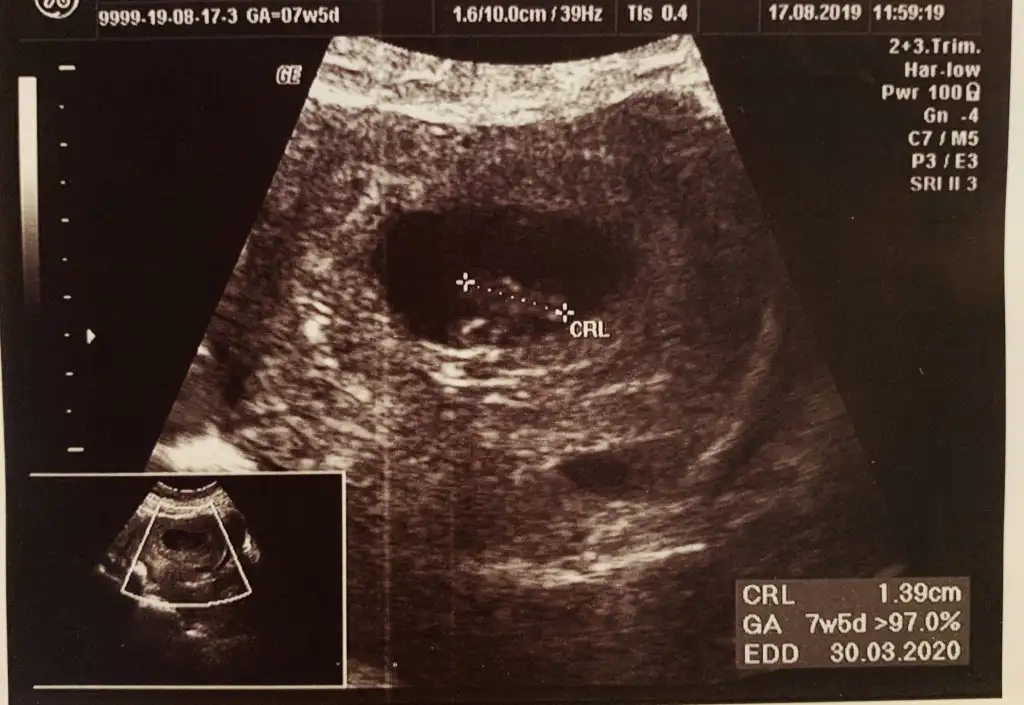

Buda benim minnoş 5 hafta 5 günlükken vajinal ultrason görüntüsü kalp atışını duyamadım ama gördük çok şükür

5+5 göre erkek 7+5 olmuyor kese konumu artık bebek yer değiştiriyor o haftalarda dediğim gibi kese tutmaya biliyor en iyi sonuç nub teorisi bakalım sizde kese tutacakmı 5+5 göre erkek tatlım